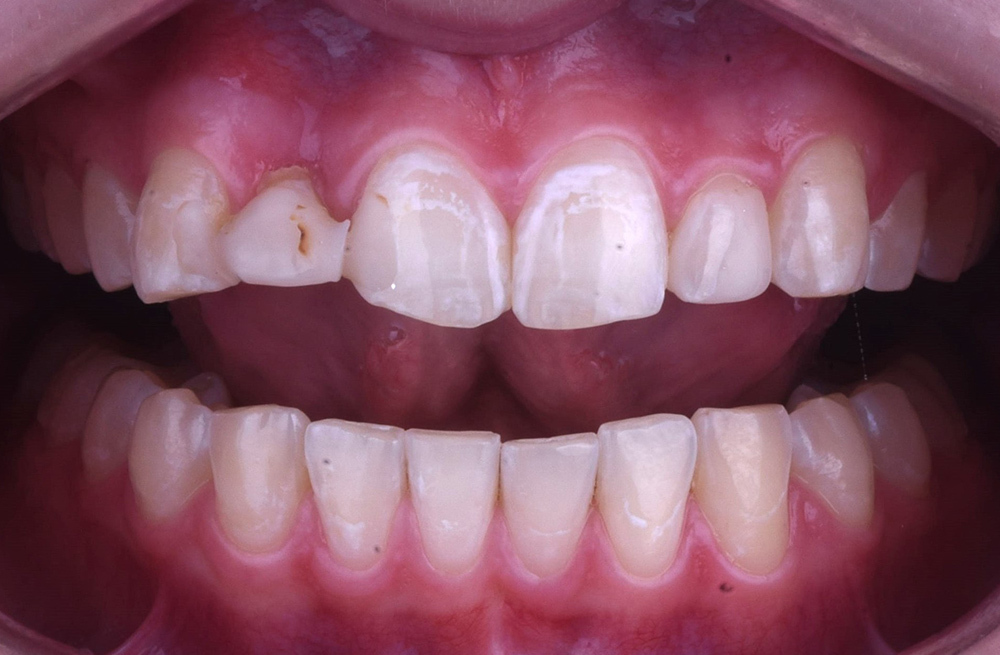

Эстетическая реабилитация винирами при генерализованной стираемости зубов